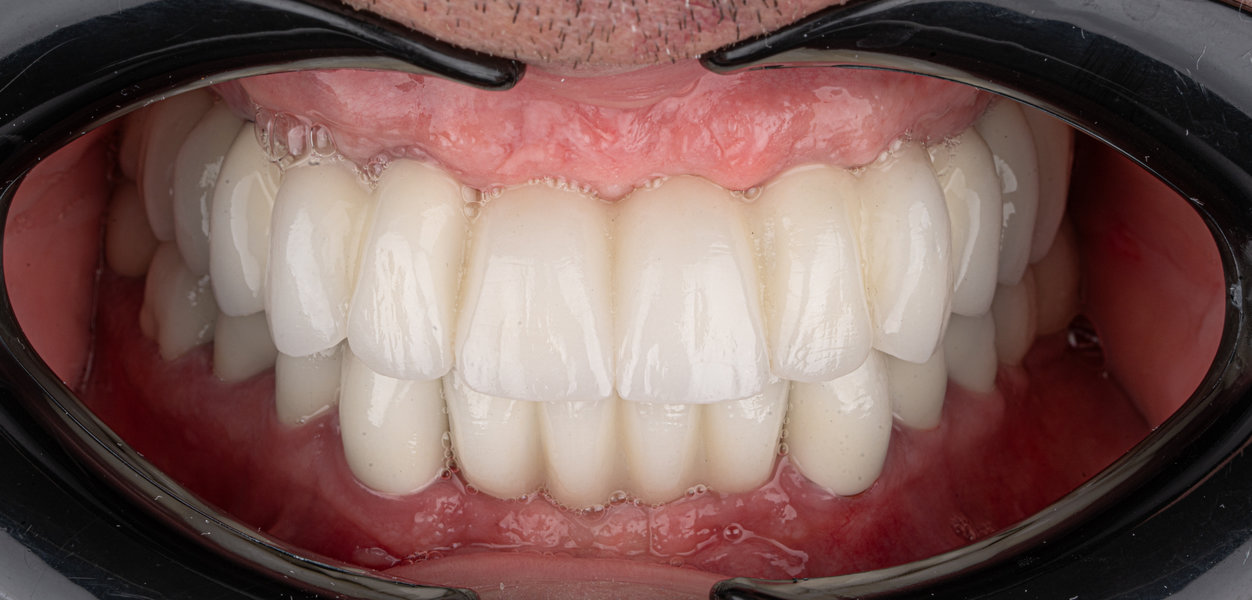

Caz 2